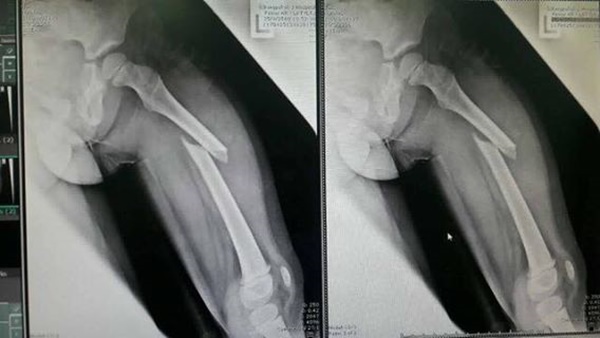

หลังจากนั้นเด็กยืนขึ้น แต่ยืนไม่ตรง เจ้าหน้าที่พาไปนวดขาก็ไม่ดีขึ้น พอพาไปโรงพยาบาลพบว่ากระดูกต้นขาด้านซ้ายหัก ต้องรักษาด้วยการดึงขาให้กระดูกประสานและใส่เฝือกดามไว้ นอกจากนี้ตัวแทนสวนน้ำได้ฝากเงินไว้ 1,000 บาท บอกจะรับผิดชอบ

ต่อมาผู้สื่อข่าวได้เข้าไปพบกับเด็กหญิงคนดังกล่าว พบว่าเด็กยังคงใส่เฝือกที่เท้าซ้ายยาวจนถึงสะโพก มีอาการปวดตลอด ครอบครัวนางสาวจิรากรต้องช่วยกันดูแล